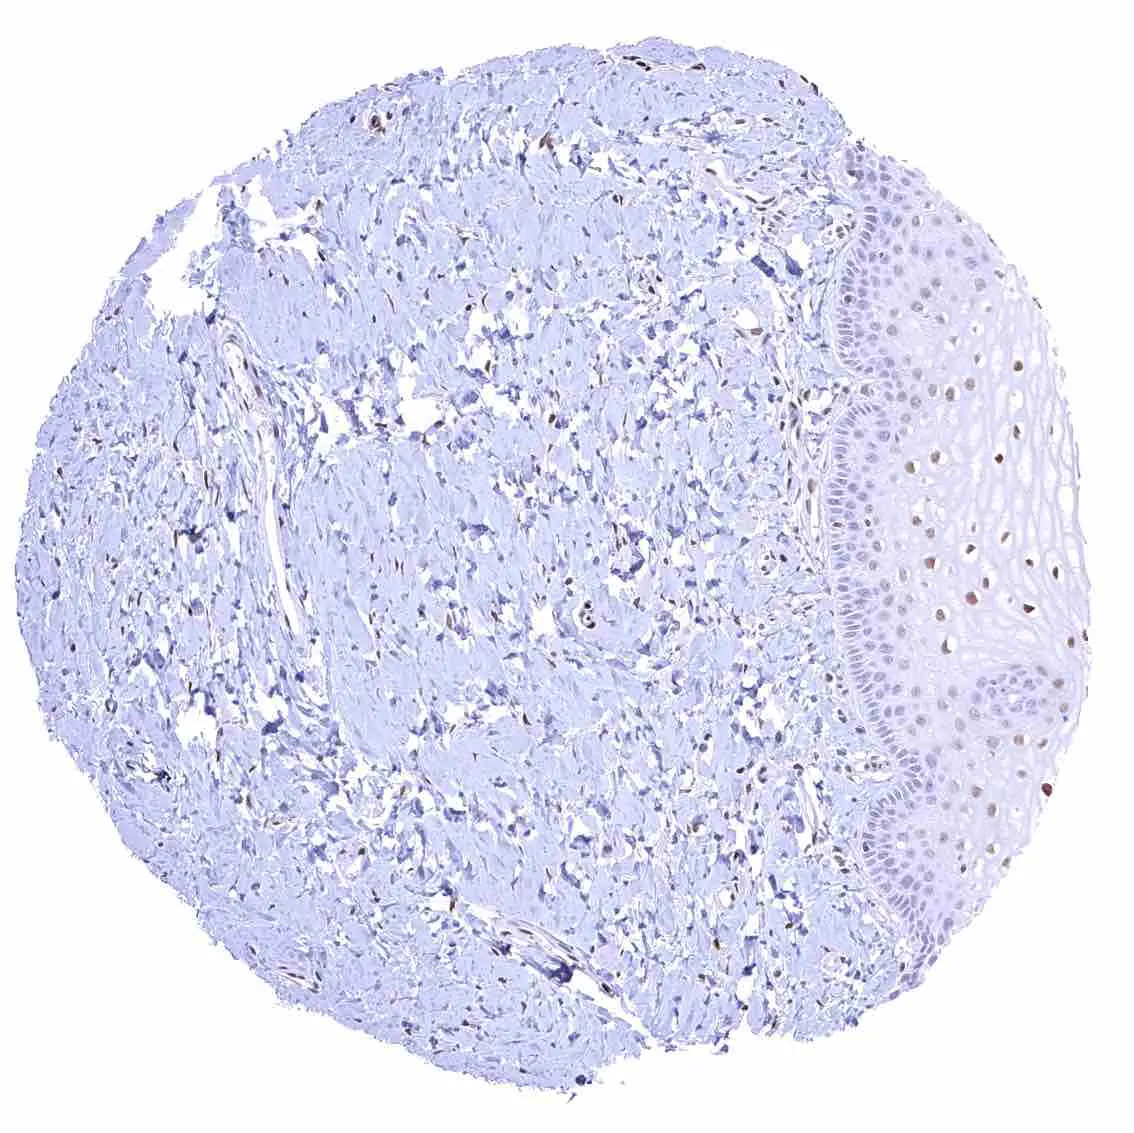

Appendix, mucosa – Among epithelial cells, nuclear p27 staining predominates in superficial epithelial cells. Most p27 staining occurs in lymphatic cells, however.